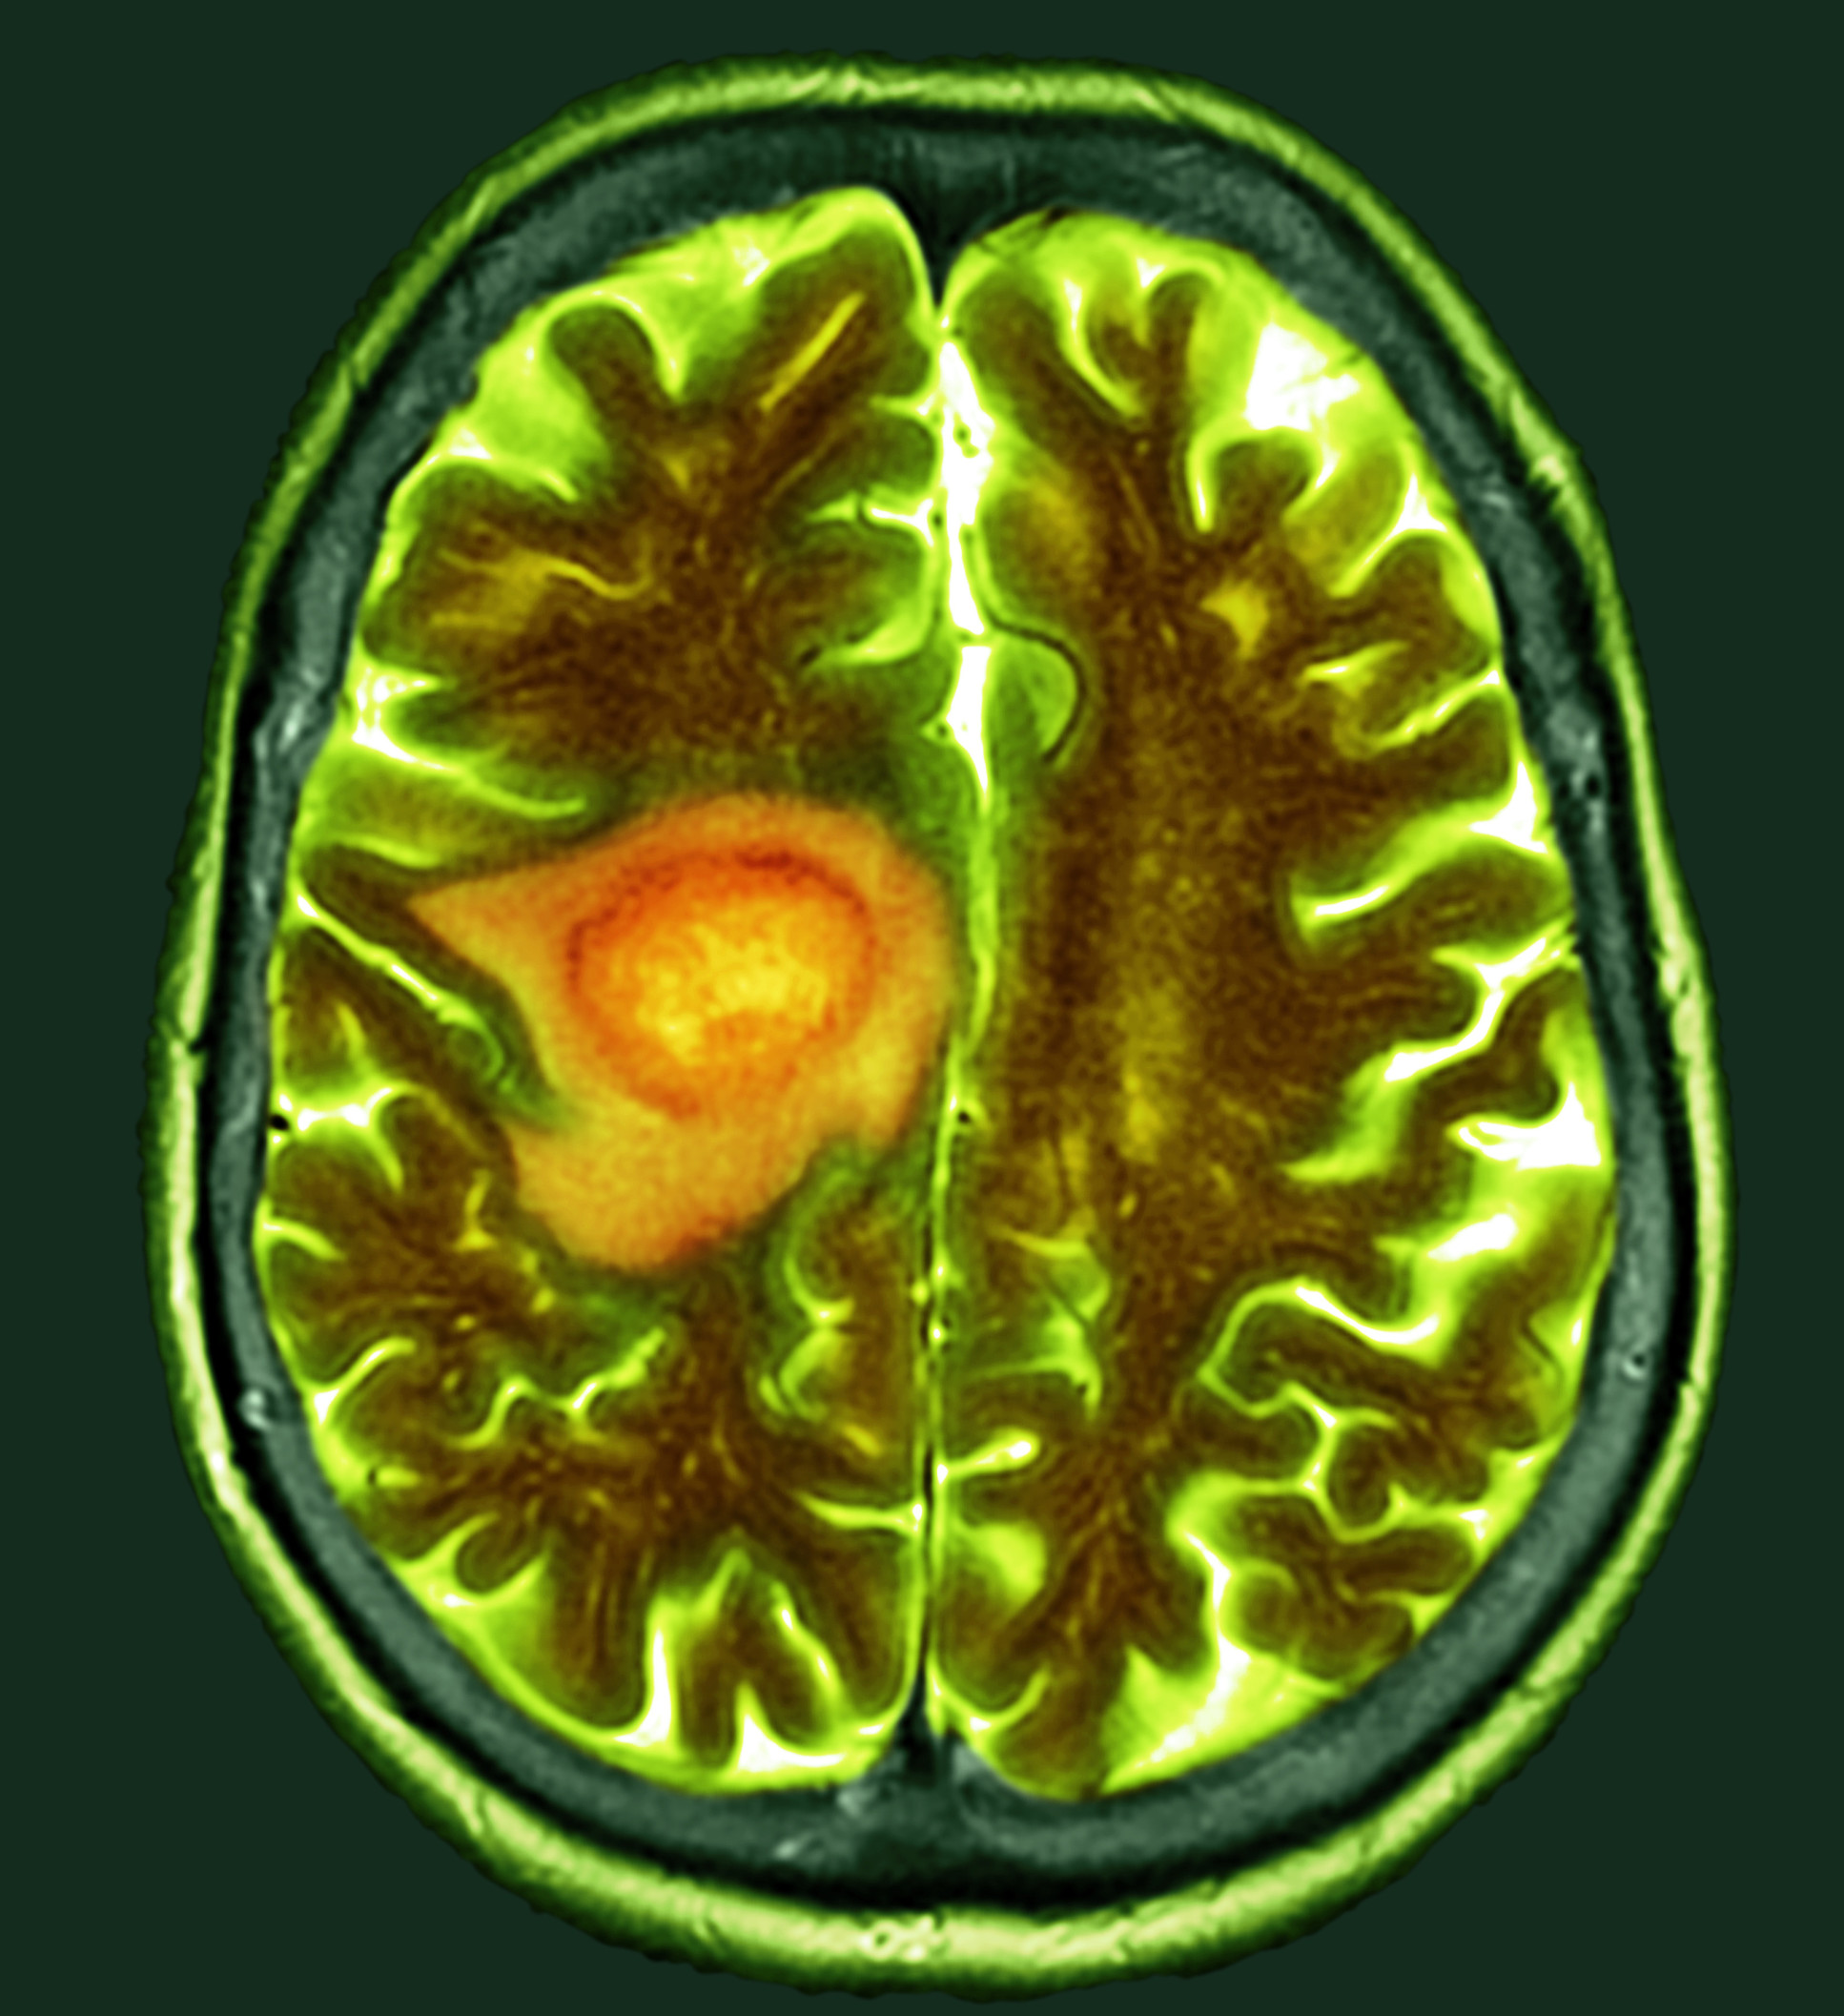

All cells in the human body contain mitochondria, structures that produce energy and biomolecules for whatever activity the cells need to carry out. Looking closely at the cells involved in glioblastoma, one of the most aggressive and deadliest forms of cancer, revealed that their mitochondria are extraordinarily efficient.

It’s an approach that could be applied to many other kinds of cancer. “But we are particularly interested in glioblastoma, because there is no effective treatment and no cure.”